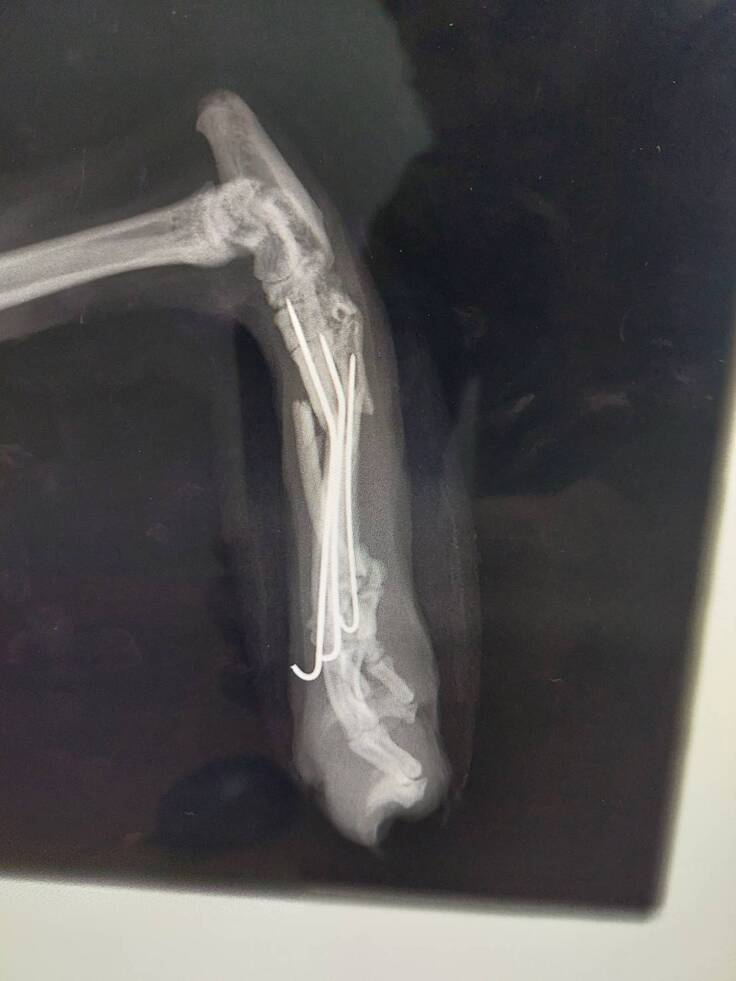

足を絡ませて高い所から落ちてしまったテディは

足の骨を一度に4本骨折してしまうという

人間でも我慢できないであろう痛みに耐えています。

とても細い骨なので、難しいと言われた手術でしたが

なんとかピンをいれて固定していました。

通常1カ月もすれば骨が固まってくるのですが

テディは免疫不全のため4カ月たった今も

骨がくっついていません。

長い間固定し続けた足も皮膚がただれてしまい

今はギプスを外しています。